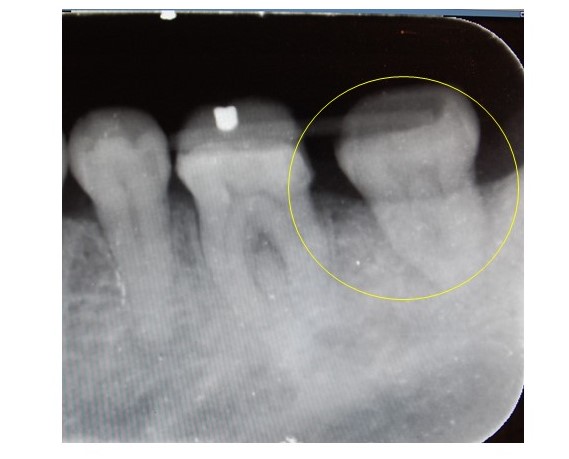

11ヶ月後のレントゲン画像です。第二大臼歯の周囲に歯槽骨の添加(再生)が認められます。歯周ポケットは近心遠心中央ともに4㎜と改善され、歯牙の動揺も軽減しました。

症状が安定しているので被せ物を作成し、メンテナンスで経過をみていきます。